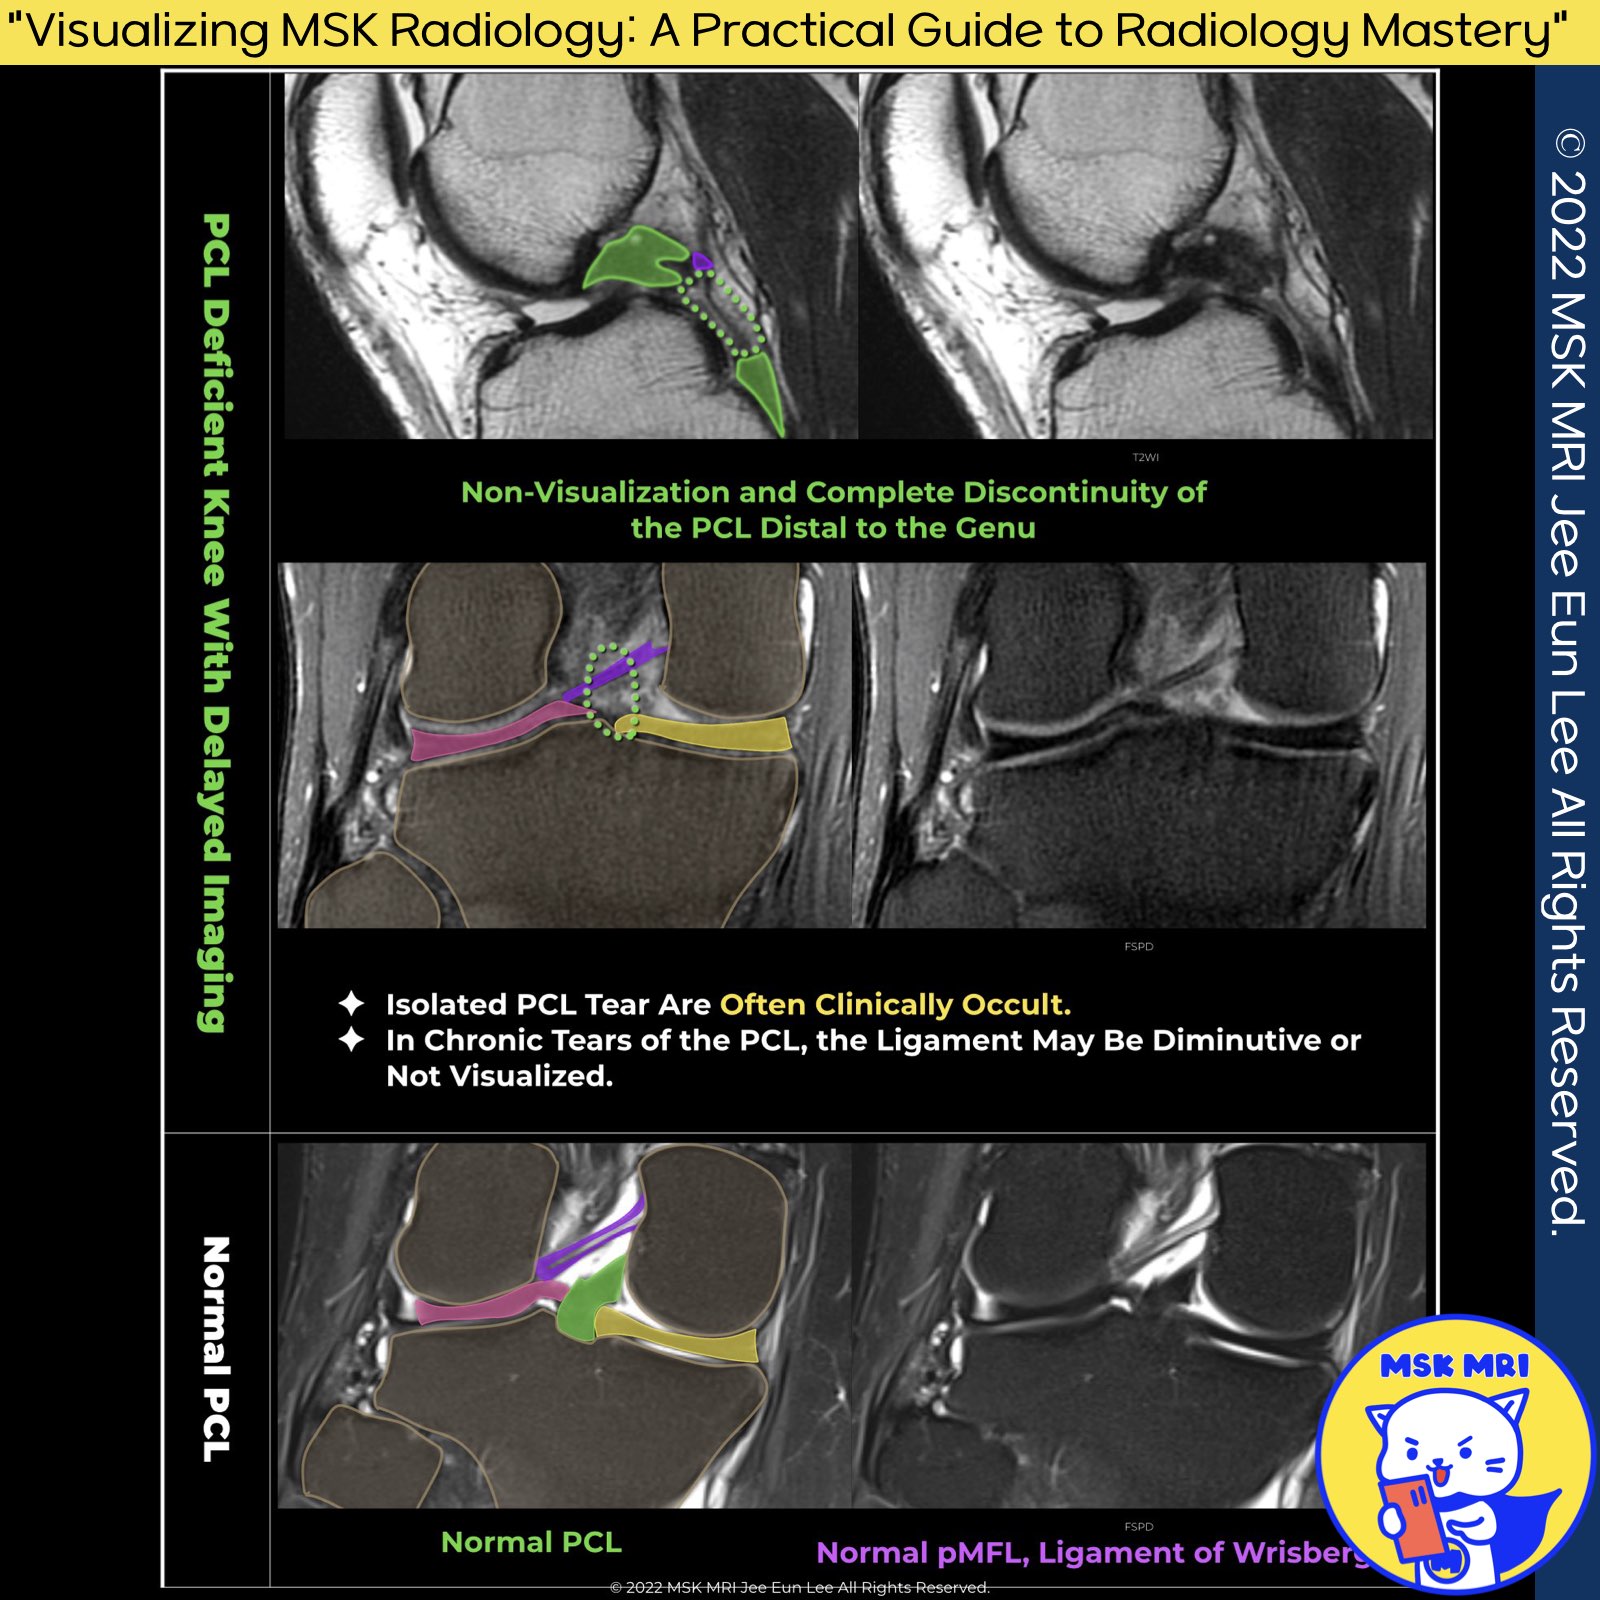

1️⃣ Chronic PCL Tears: MR Imaging Insights

✅MR imaging for chronic PCL injuries is less reliable, often confusing ligament continuity with partial or no tears. Identifying chronic partial tears is difficult, even with clinical indicators.

✅ Chronic PCL damage may show ligament thickening or elongation, with abnormal shape but seldom discontinuity.

✅In studies, 28% of chronic PCL injuries appeared nearly normal on MRI, while 44% showed ligament continuity with morphologic abnormalities.